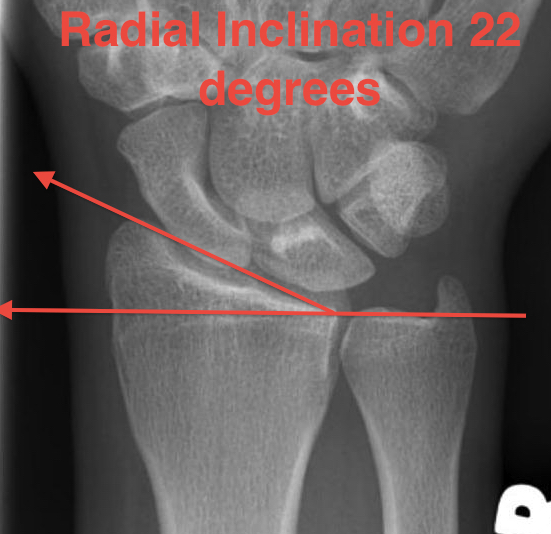

Radial angles

| Volar tilt mean 11° | Radial inclination mean 22° | Radius mean 11 mm longer than ulna |